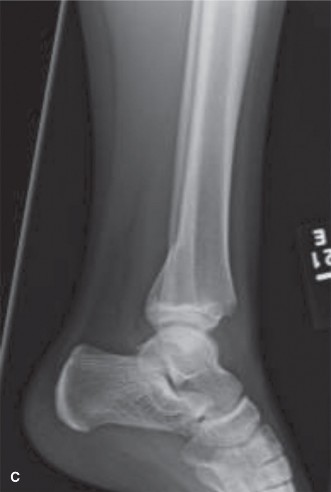

While standard radiography is sufficient for the majority of pediatric diaphyseal and metaphyseal fractures, advanced imaging modalities are critical for evaluating complex intra-articular fractures, transitional fractures of the distal tibia (such as Tillaux or triplane fractures), and injuries involving the cartilaginous epiphysis.

In cases where a lateral condyle fracture is suspected but displacement is ambiguous, an internal oblique radiograph or a magnetic resonance imaging scan may be indicated to assess the integrity of the cartilaginous hinge. If the cartilaginous hinge is intact, the fracture may be treated with closed reduction and percutaneous pinning or cast immobilization. If the hinge is disrupted, open reduction is mandatory to prevent nonunion, cubitus valgus deformity, and tardy ulnar nerve palsy. Computed tomography with three-dimensional reconstruction is invaluable for preoperative planning in complex physeal fractures, allowing the surgeon to visualize the exact plane of the fracture lines and plan lag screw trajectories that minimize physeal violation.

Case Eight Distal Tibial Transitional Fractures

These include the Tillaux fracture (Salter-Harris III of the anterolateral distal tibia) and the Triplane fracture (Salter-Harris IV equivalent occurring in three planes). These occur during the asymmetrical closure of the distal tibial physis (closing central to medial to lateral). Displacement greater than 2 millimeters requires open or arthroscopically assisted reduction and internal fixation to prevent post-traumatic arthritis. Fixation is typically achieved with epiphyseal or metaphyseal parallel cannulated lag screws, ensuring no screws cross the remaining open physis.